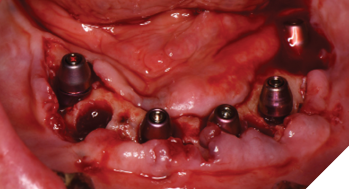

Three weeks later, the patient returned for treatment of the mandible (Figs. 13A, 13B). Teeth 22,23,24 were extracted and implants 19,21 and 27 were removed. A surgical guide with computer guided surgery was used to prepare the osteotomies and place the implants (Figs. 14A, 14B). Implants (Genesis Active – Keystone Dental) were placed in tooth positions 19,20,23,26 and 30. Allograft bone grafts were placed into the extraction sockets and all intraboney defects. Multiunit abutments were inserted on all implants and torqued to 30ncm (Fig. 15). The soft tissues were sutured closed. A rapid denture conversion system was used to efficiently convert a denture into a fixed provisional restoration.20 (EasyPro – Keystone Dental). This denture conversion system maintained the structural integrity of the denture while maintaining an esthetic provisional restoration (Figs. 16A-D).

Fig. 14A

Fig. 14B

Fig. 15